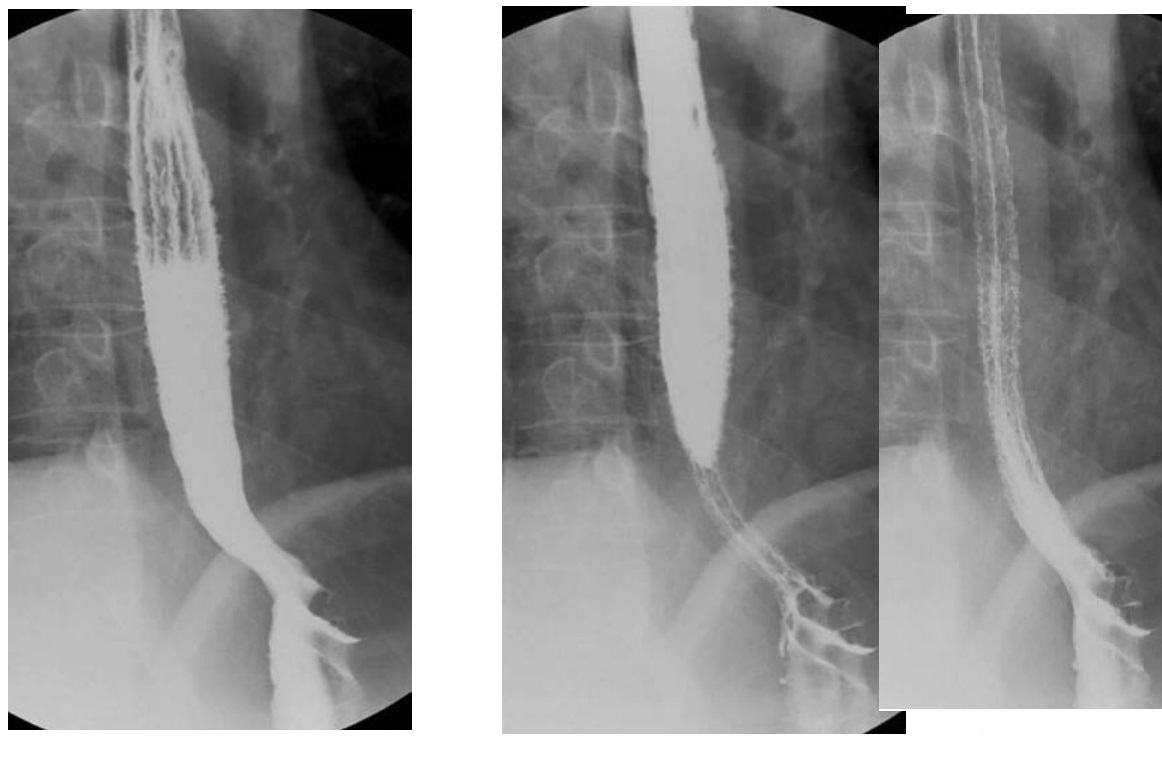

Oesophageal pseudodiverticulosis

Barium - multiple, tiny (1- to 4-mm depth), flask-like outpouchings in the oesophagus

Barium trapped in dilated excretory ducts of submucosal glands

CHRONIC REFLUX* and Candida